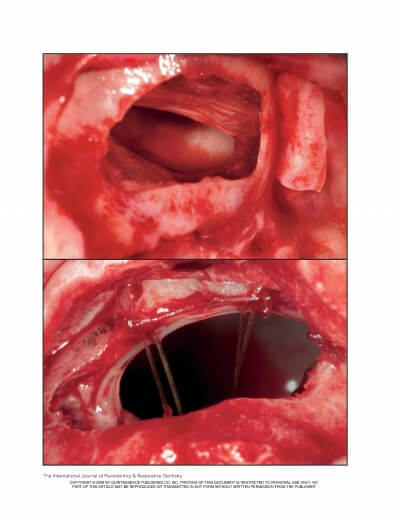

MAXILLARY SINUS AUGMENTATION- 3 CASES

SINUS FLOOR AUGMENTATION WITH HYDROPNEUMATIC TECHNIQUE

SINUS AUGMENTATION PROCEDURES